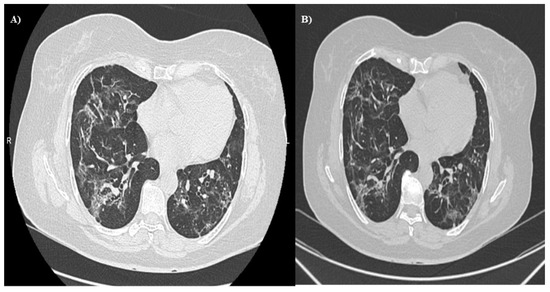

- Cherrez-Ojeda, I.; Robles-Velasco, K.; Osorio, M.F.; Cottin, V.; Vergara Centeno, J.; Felix, M. Follow-up of Two Cases of Suspected Interstitial Lung Disease Following Severe COVID-19 Infection Shows Persistent Changes in Imaging and Lung Function. Clin. Case Rep. 2021, 9, e04918. [Google Scholar] [CrossRef]